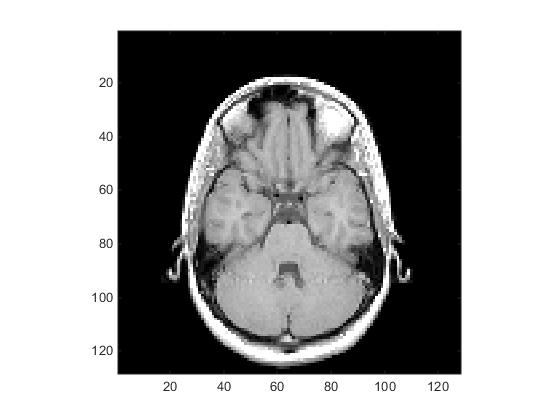

Чтобы отобразить одно из изображений МРТ, используйте image команда:

figure colormap(map) image_num = 8; image(D(:,:,image_num)) axis image

Сохраните пределы осей X и Y для использования в следующей части примера:

x = xlim; y = ylim;